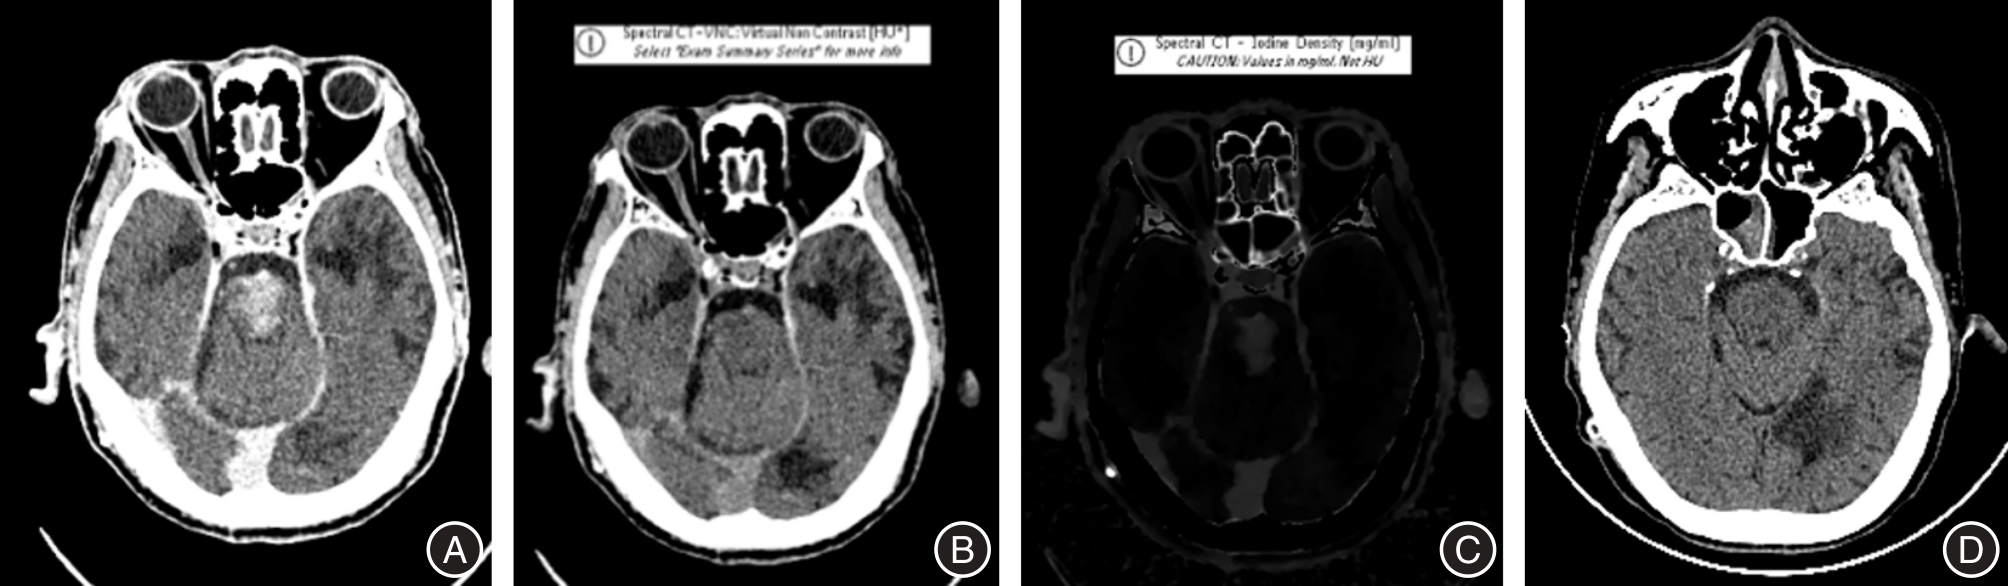

GULKO E, ALI S, GOMES W, et al. Differentiation of hemorrhage from contrast enhancement using dual-layer spectral CT in patients transferred for acute stroke[J]. Clin Imag, 2020, 69: 75-78. doi:10.1016/j.clinimag.2020.06.046

BERNSEN M L E, VEENDRICK P B, MARTENS J M, et al. Initial experience with dual-layer detector spectral CT for diagnosis of blood or contrast after endovascular treatment for ischemic stroke[J]. Neuroradiol, 2022, 64(1): 69-76. doi:10.1007/s00234-021-02736-5

RIEDERER I, FINGERLE A A, ZIMMER C, et al. Potential of dual-layer spectral CT for the differentiation between hemorrhage and iodinated contrast medium in the brain after endovascular treatment of ischemic stroke patients[J]. Clin Imaging, 2021, 79: 158-164. doi:10.1016/j.clinimag.2021.04.020